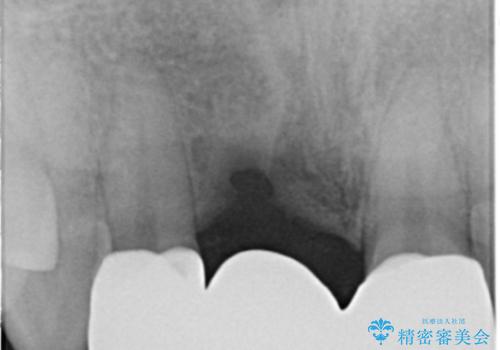

- 前歯ブリッジのやり変えを希望され来院された患者様です。

審美性を重視されていたので、オールセラミッククラウン(スペシャル)でのブリッジを選択されました。

周りの歯との色調に合わせた綺麗なブリッジを入れることができました。